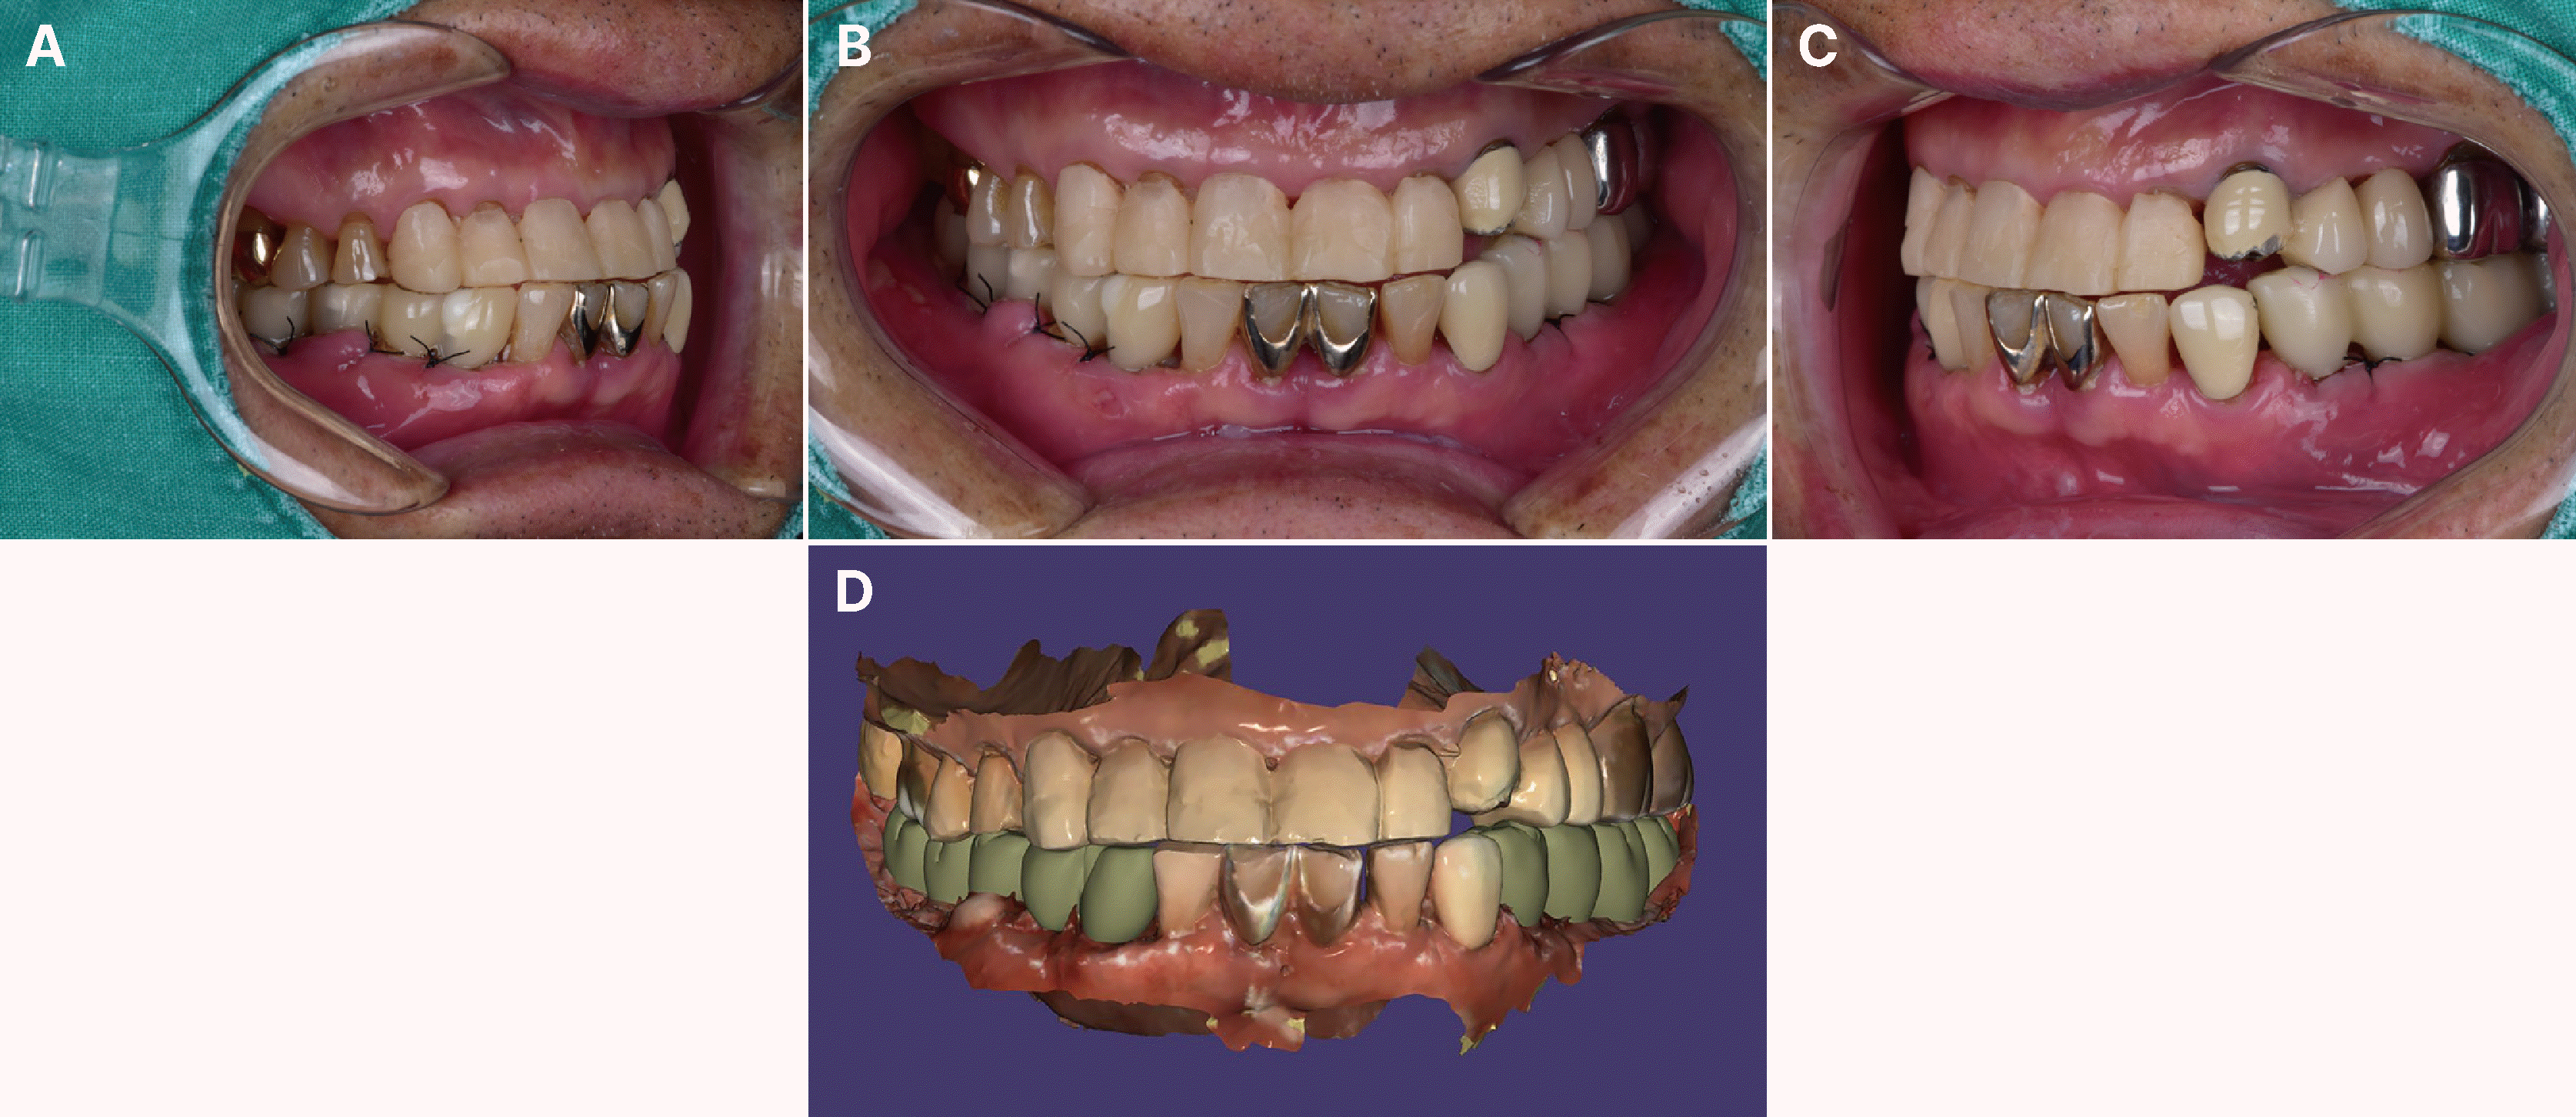

Fig. 2

Initial oral examination. Severe attrition of both maxillary and mandibular anterior dentitions with anterior cross-bite is shown.

Fig. 4

Images of the provisional crowns for both anterior and posterior teeth are presented. (A - C) Delivery of provisional crowns on maxillary anterior and mandibular posterior areas in a proper CR position, (D) A digital image depicting the provisional state is shown.

At the initial visit, the patient exhibited a skeletal Class III relationship with edge-to-edge incisal contact in CR guided by chin-point technique (Fig. 1). TMJ assessment showed normal mouth opening (> 40 mm) without joint or muscle symptoms, and no signs of popping, crepitus, or pain on loading test (per Dawson).7 Habitually, the mandible closed anterosuperiorly, with the mandibular incisors sliding along the labial surfaces of the maxillary incisors (Fig. 2). Treatment commenced with the mandible guided into CR, achieving stable anterior end-to-end contact at the appropriate vertical dimension.

CR guidance revealed anterior extrusion and premature contact (teeth #11, 21), with a 42 mm vestibular distance and a 2 mm excess in subnasion-gnathion distance relative to the outer canthus-labial commissure distance (Willis method), indicating facial elongation. Consequently, a 2 mm anterior VD reduction at CR was planned. Final VD integrated vestibular measurement (40 mm), Willis analysis, facial aesthetics, and prosthetic requirements.8 Tooth preparation and provisionalization of #11-13 and #21-22, followed by occlusal adjustment, established stable anterior guidance at clinician-guided CR and VD, enabling immediate stable mandibular closure.